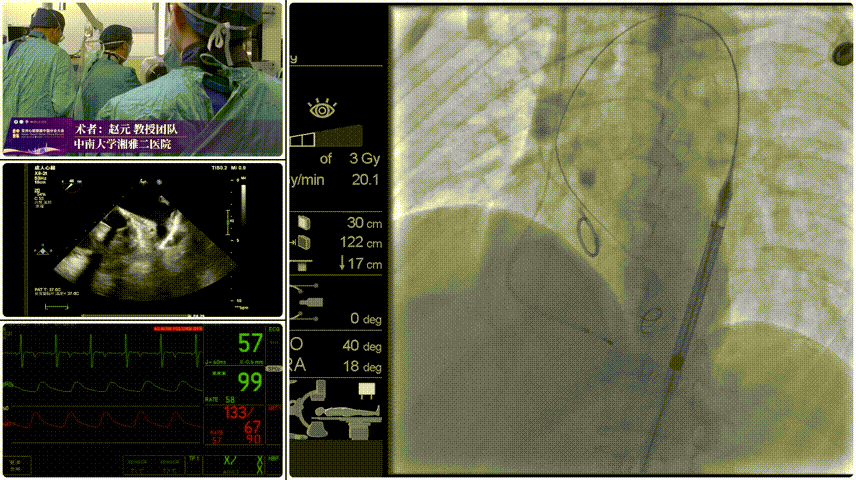

Step 1.柔顺过弓:精湛手术操作+优异通过性能、复杂弓形无任何辅助一次通过。

Step 2.定位释放:初始高定位,使瓣膜自然下滑至理想位置。

Step 3.工作位评估:位置合适,深放以避免瓣膜开合区过度受挤压。

Step 4.稳定脱钩无位移。

Step 5.最终造影:位置合适,瓣膜形态良好,无瓣周漏。

患者压差由105mmHg降至17mmHg。

手术过程与术后转归

手术在全麻下进行,团队选择右股动脉作为主入路,凭借器械柔顺性优势一次性顺利过弓,精准抵达瓣环位置。通过多角度造影确认瓣膜同轴性良好后,逐步释放瓣膜,脱钩过程稳定无位移。术后即刻造影显示,瓣膜位置理想,无瓣周漏;超声评估提示左心室收缩功能正常,跨瓣压差显著改善,患者胸闷、气促症状明显缓解。术后 24 小时患者即可下床活动,72 小时顺利出院,未发生卒中、血管并发症、传导阻滞等不良事件。